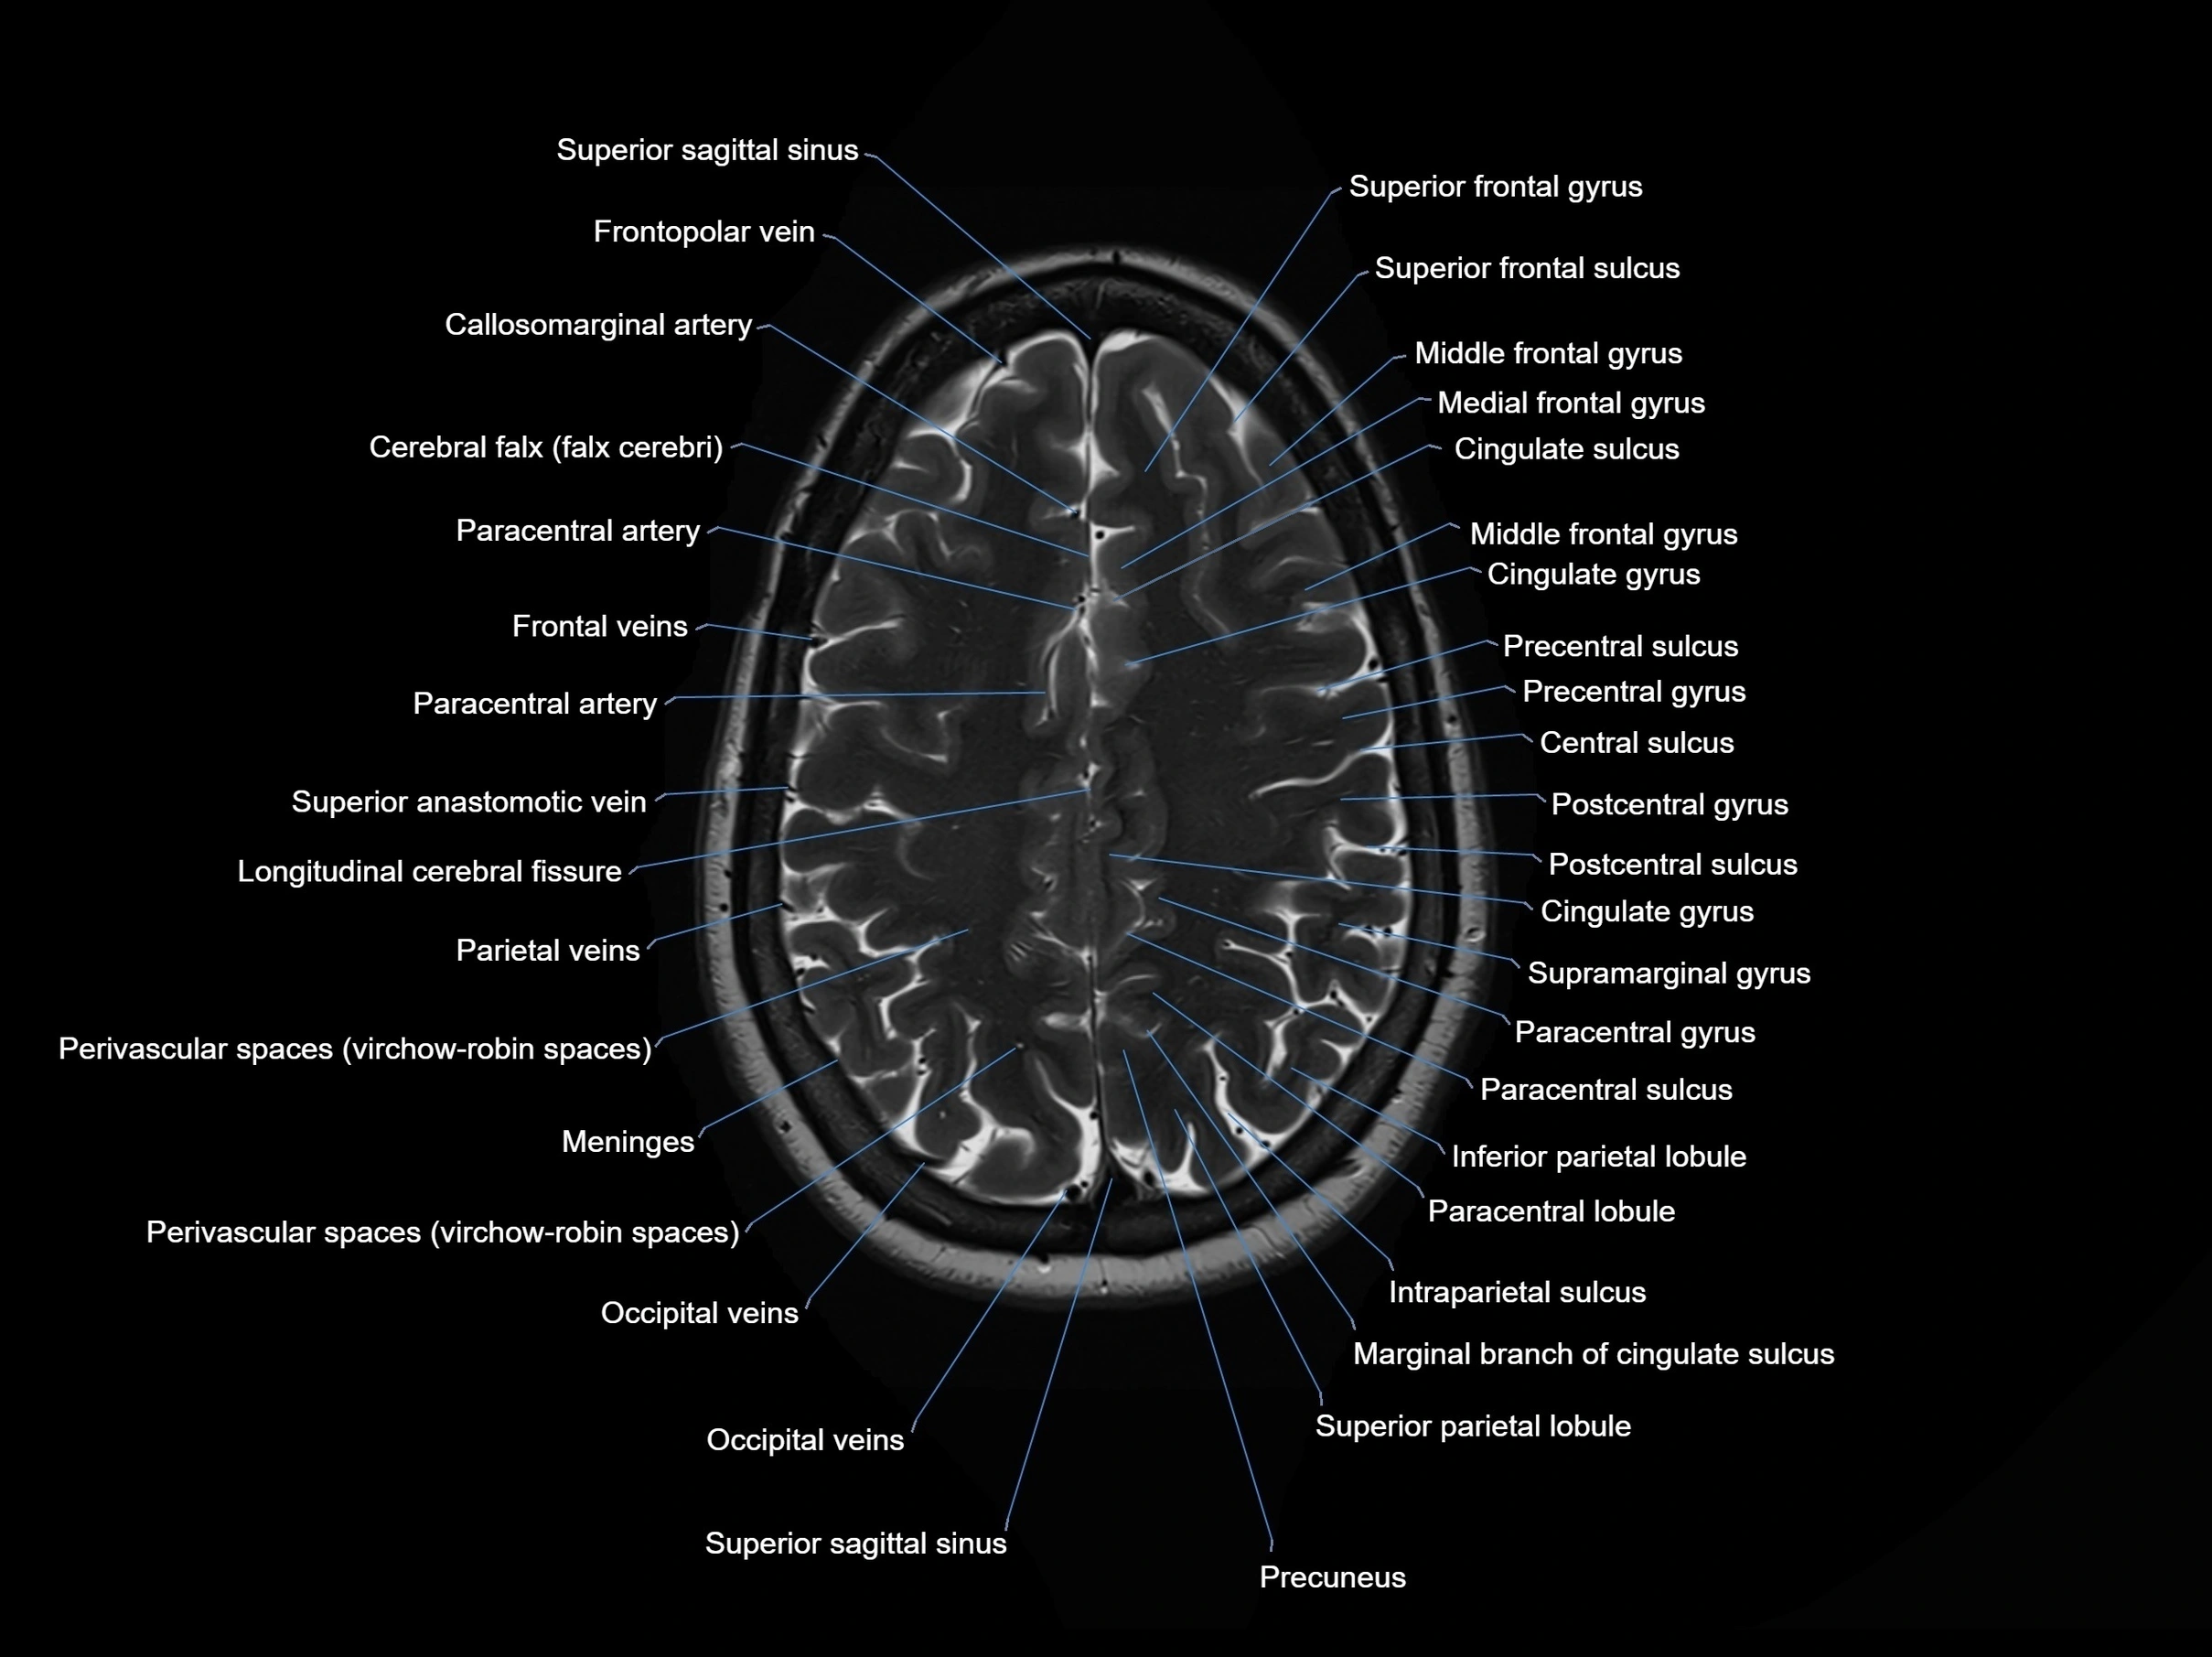

MRI images